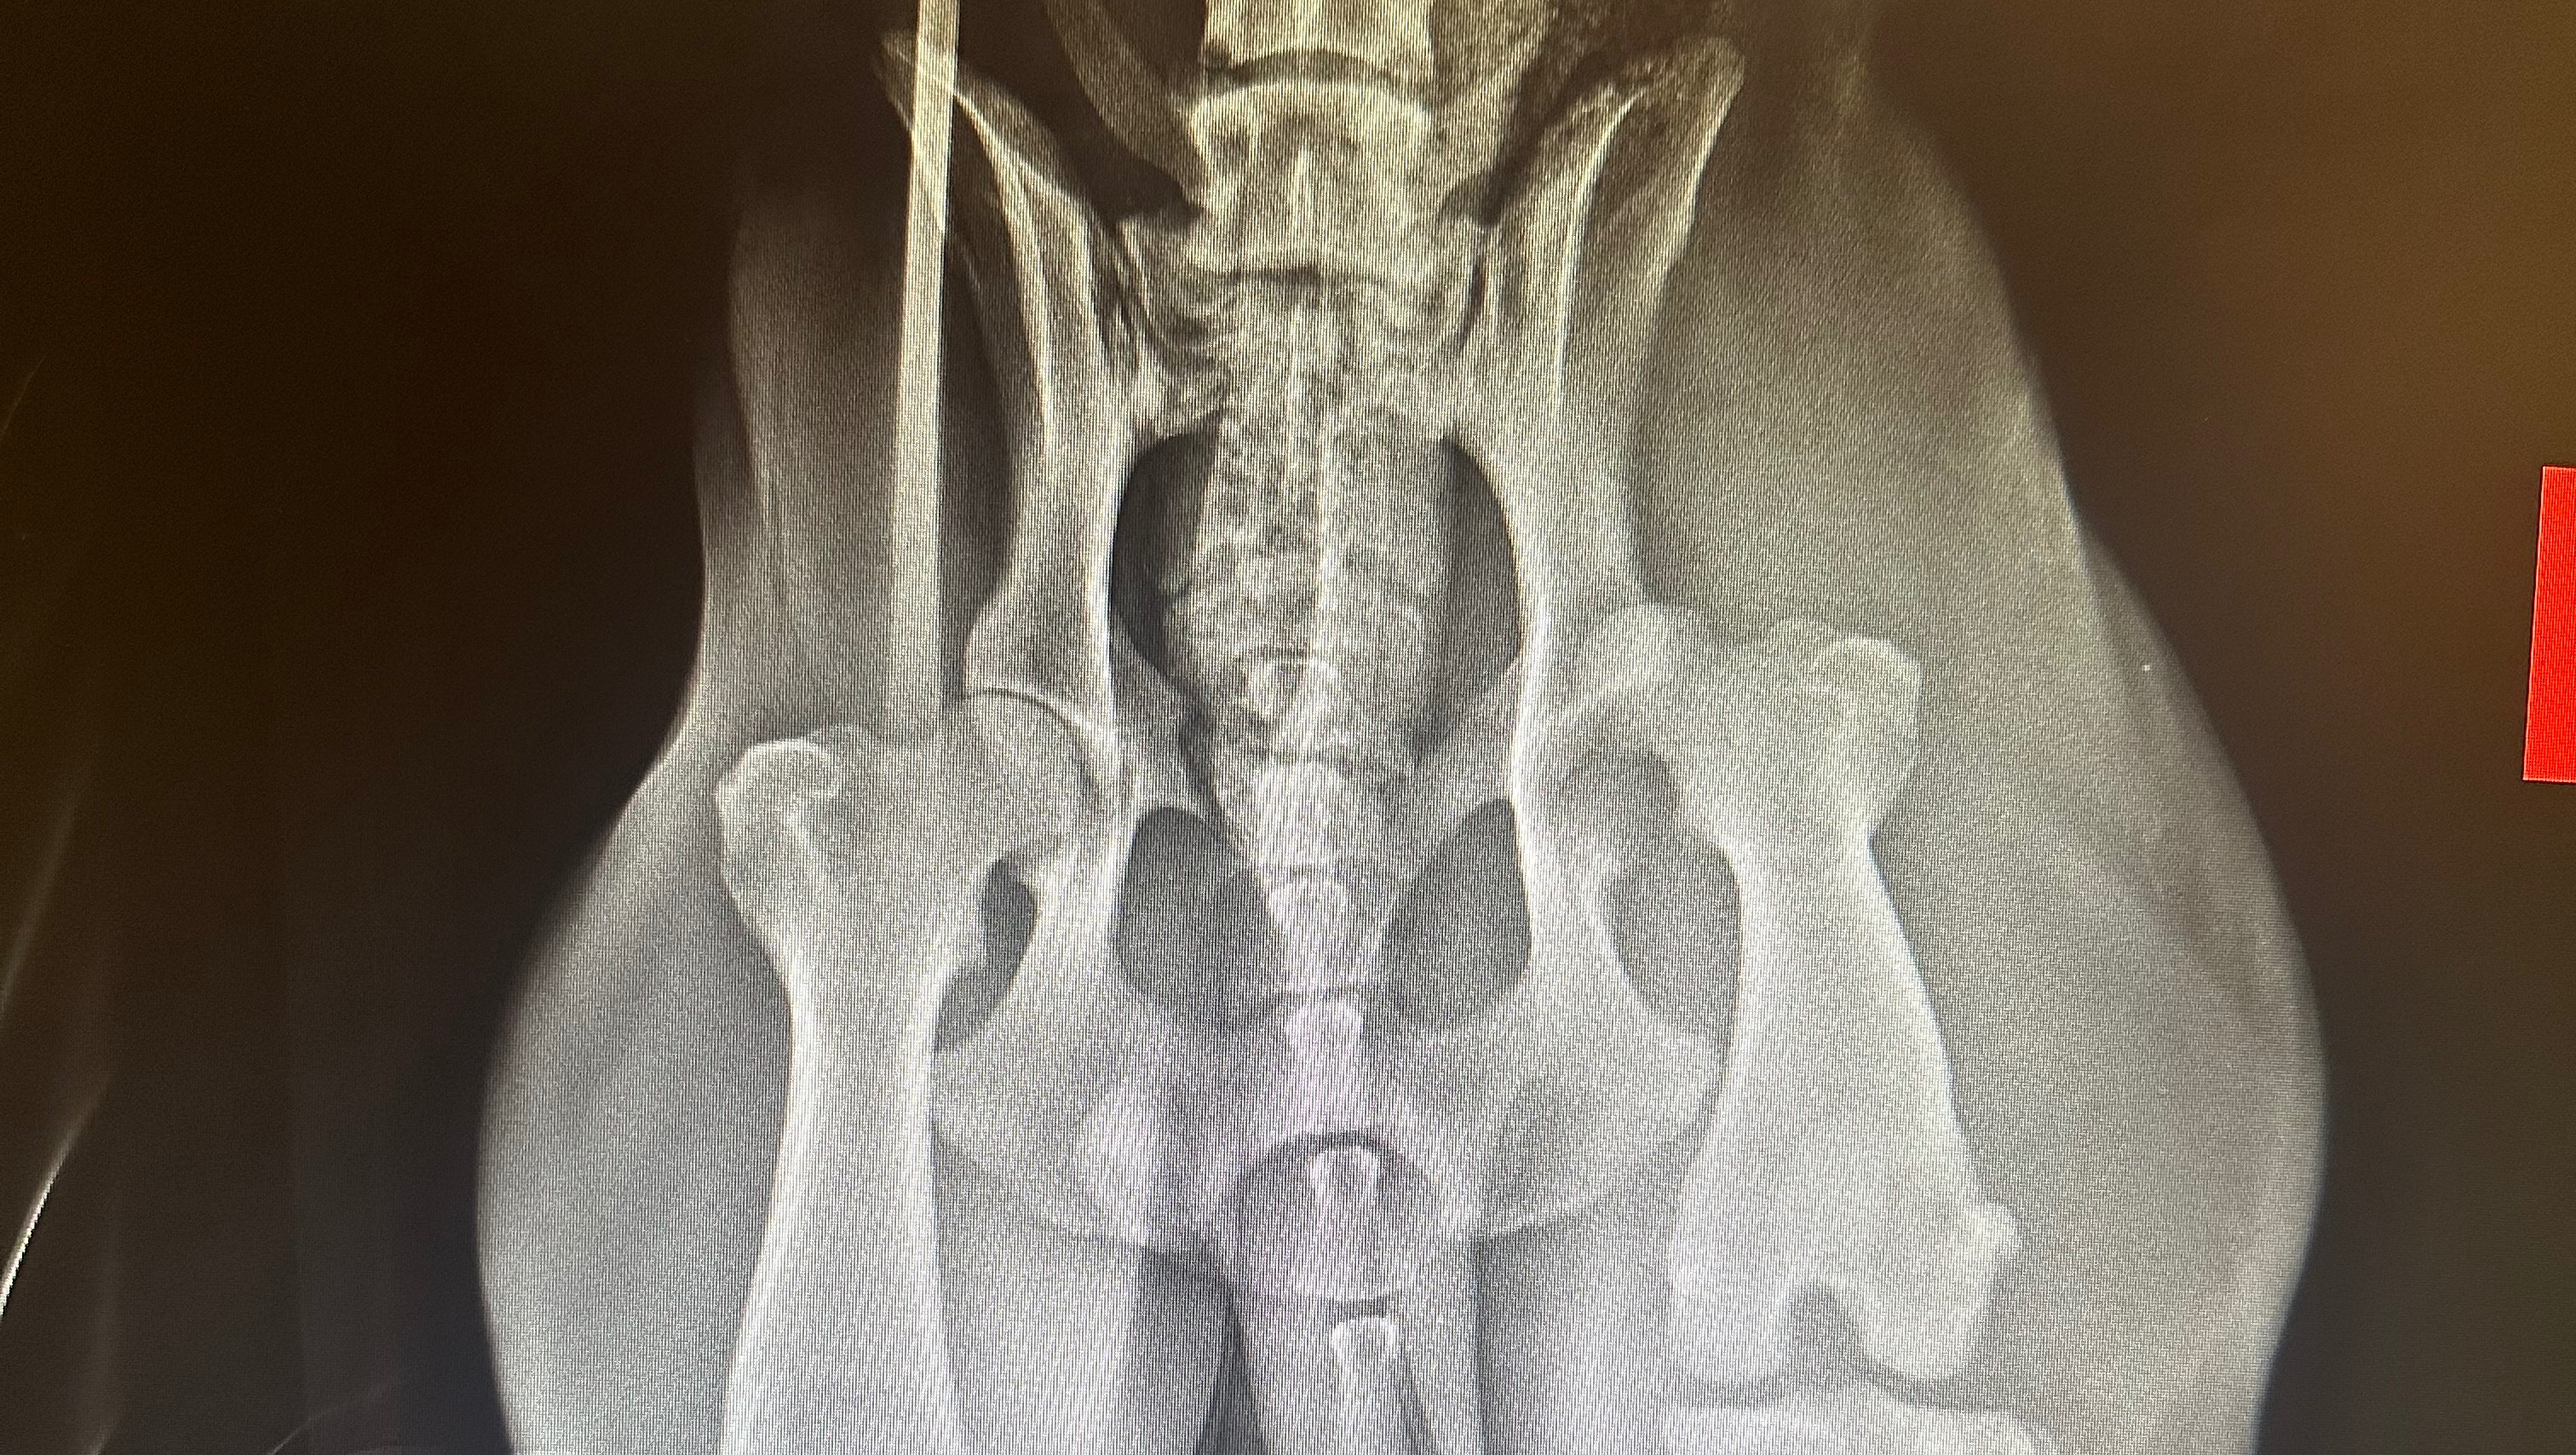

to get into a vet ASAP! This poor boy has been through so much in his only 1.5 years of life. He was shot and still has the bullets in him, luckily the bullets aren’t affecting his day to day life but his back left hip is dislocated and he will be needing an expensive surgery called a FHO (femoral head ostectomy) We don’t know much of his background but he has the sweetest personality and I’m hoping we can all come together and help give this pup the life he deserves. Any and all donations would be greatly appreciated and put towards a good cause.